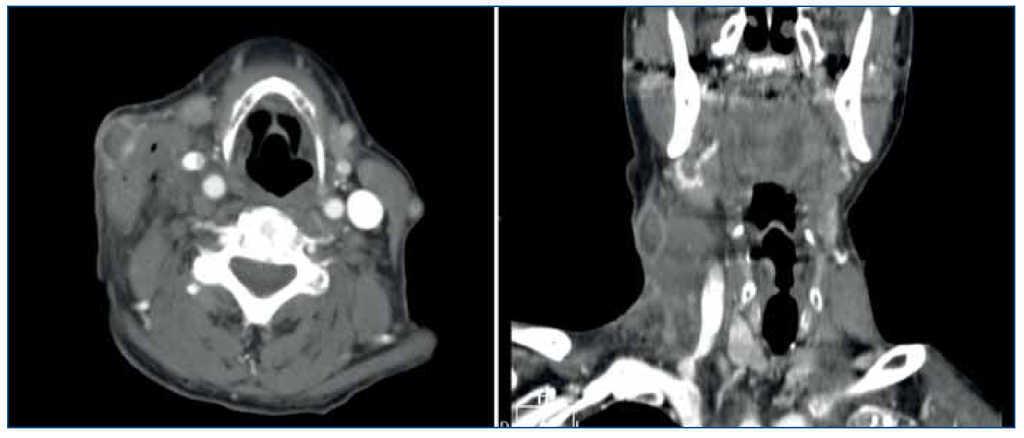

Presenta nódulo laterocervical derecho de crecimiento rápido (tres días), indoloro, sin signos inflamatorios ni repercusión sistémica. Ante la sospecha de un absceso cutáneo, se realiza incisión con drenaje sanguinolento, comenzando tratamiento antibiótico empírico. Valorado por Dermatología, establece el diagnóstico de sospecha de queratoacantoma. En la incisión quirúrgica se encuentra tumor muy friable, blanquecino, vascularizado e infiltrado hasta plano muscular superficial. La lesión es descrita histológicamente como proceso inflamatorio granulomatoso y supurativo con hiperplasia epidérmica pseudoepiteliomatosa, tractos de drenaje, áreas de necrosis, agregados epitelioides y células gigantes multinucleadas de tipo cuerpo extraño fagocitando fibras elastósicas, llegando a tejido muscular esquelético, compatible con pioderma blastomicoide. Los cultivos con y sin antibioterapia (vancomicina-ceftazidima) resultan negativos. Se realiza tomografía computarizada, observándose conglomerado adenopático laterocervical medio e inferior derecho con importante componente de partes blandas asociado, sugestivo de proceso neoformativo frente a proceso inflamatorio infeccioso (figura 1).

Figura 1.Tomografía computarizada inicial.

Dos meses tras la retirada de los tuberculostáticos, el estudio radiológico comparativo no observó adenopatías cervicales de tamaño significativo y los planos grasos cervicales estaban conservados (figura 2).

Figura 2.Tomografía computarizada postratamiento.